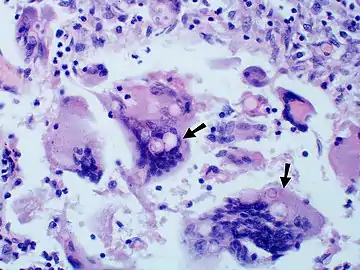

- Granuloma with early suppuration. Fungal organisms difficult to recognize at this low magnification.

- Large yeast-like fungi seen within giant cells at arrows.

- Large yeast-like fungi seen within giant cells at arrows. Budding yeasts in cytoplasm of giant cells at arrows. Broad-based budding and double contoured cell wall seen in the giant cell in the center is characteristic of Blastomyces dermatitidis.